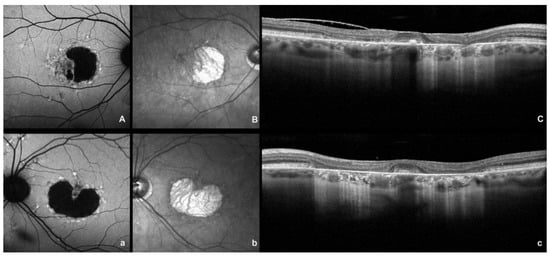

2. Fundus Autofluorescence and Near Infrared Autofluorescence

3. Fluorescein Angiography and Indocyanine Green Angiography

4. Optical Coherence Tomography Angiography and Spectral Domain Optical Coherence Tomography

5. Hyperreflective Foci